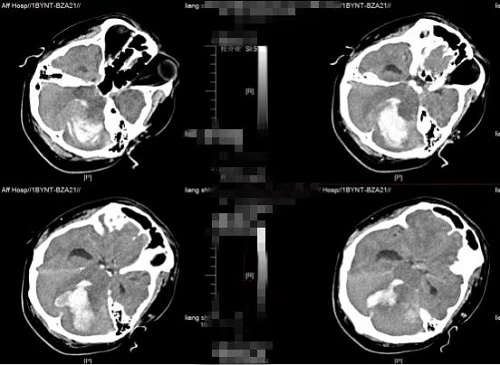

明确诊断后,各科室争分夺秒快速完善各项术前准备工作。从桂先生入院到进入手术室,耗时不到30分钟。由神经外科二区脑血管病组龙丁辉医生主刀进行手术,手术过程顺利。患者术后转入ICU,经过不间断不放弃的全力抢救后,患者的生命体征逐渐恢复到平稳状态,术后第10天转回普通病房,经过精心的术后康复治疗,患者意识清醒,出院后继续康复治疗。

图2术后CT